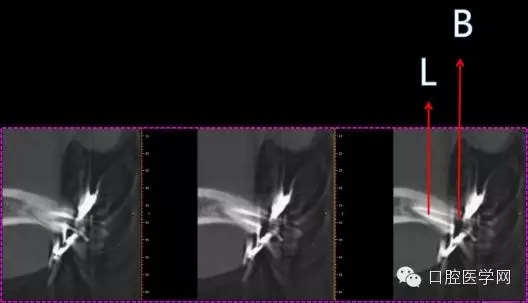

S3和Protape共同預(yù)備

B=14mm

L=18mm

根管長(zhǎng)度定位

根尖到位